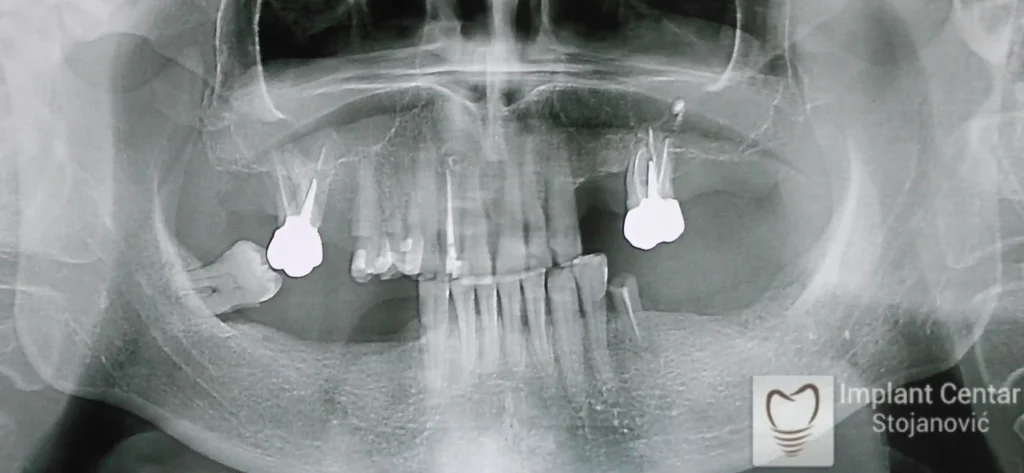

Na slici 1. i slici 2. prikazan je izgled pacijenta pre početka terapije – klinički i rendgenološki.

Nakon vađenja zuba, ugrađeni su implantati. Na slici 3 prikazan je ortopan snimak sa ugrđenim implantatima. Tokom perioda osteointegracije, pacijent je bio zbrinut fiksnim privremenim krunicama na implantatima, koje su izrađene samo dva dana nakon hirurške intervencije.